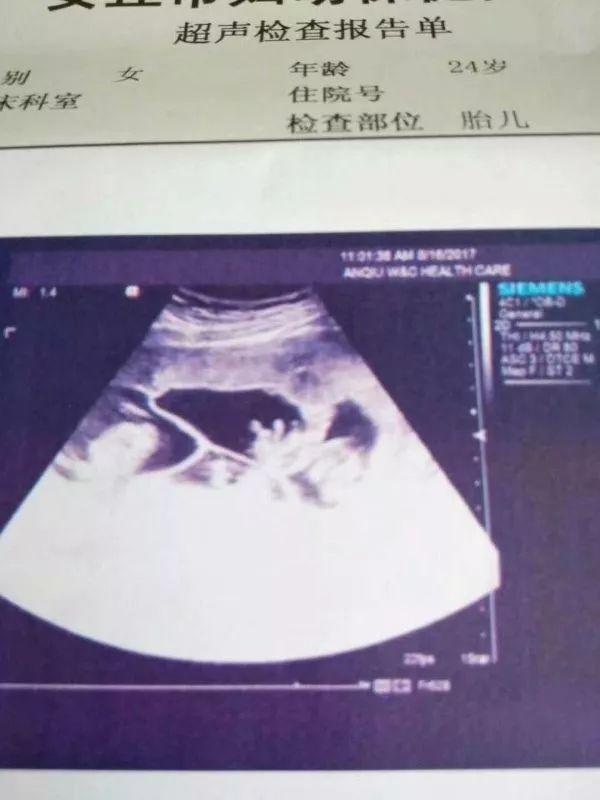

籍贯为安丘的王女士在潍坊工作,早孕检查时,有的医院诊断为三胎,有的医院不确定是三胎还是四胎,于8月16日第一次来到安丘市妇幼保健院检查,确诊为四胞胎,出于孕期安全考虑,建议减胎,但王女士心有不舍。

(安丘市妇保院确诊为四胞胎的B超影像)